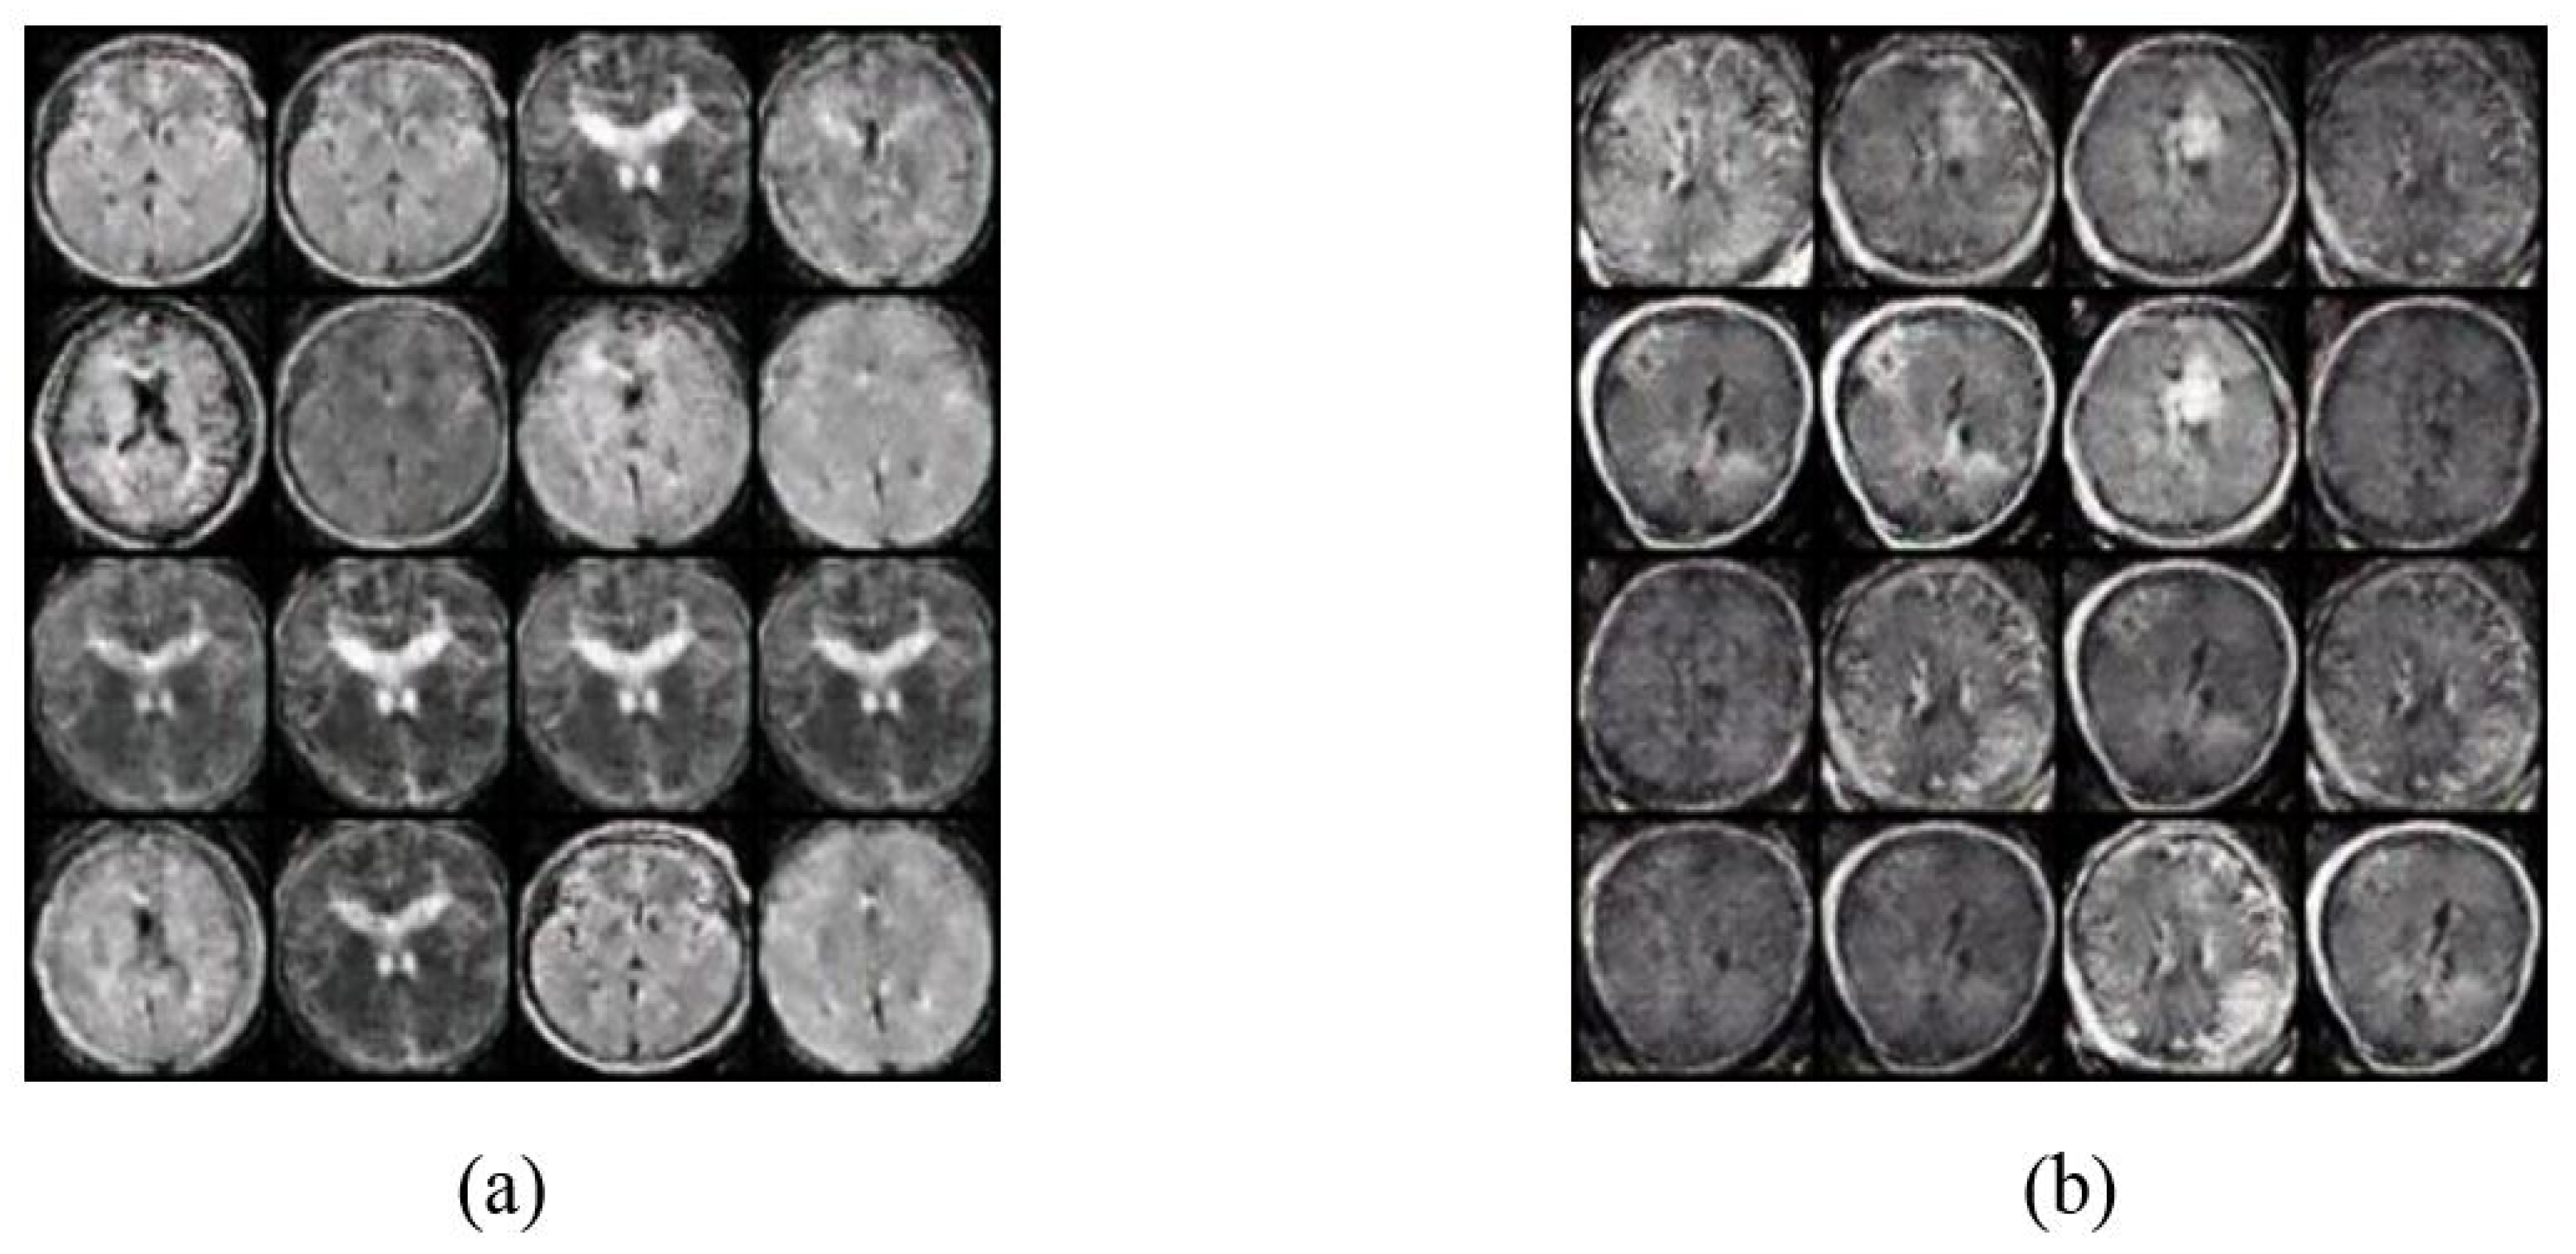

- A novel approach to automatically validate the images generated by GANs. Although manual validation may be more accurate, however, it is time-consuming and may not be practical due to the limited availability of MRI radiologists. Thus, this study proposes an automatic validation of generated images using deep transfer learning models, i.e., three models. The validation is performed by training the deep transfer models with the generated images by the two GAN architectures, i.e., Vanilla GAN and DCGAN, and then evaluating their performance on a test set composed of real brain MRI images.

4.2. Image Augmentation Using Vanilla GAN and DCGAN